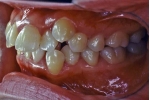

日本矯正歯科学会専門医課題症例(第3症例)

カテゴリー:Class Ⅱ division 1(抜歯症例)

大臼歯関係がclassⅡ、overjet 6mm以上、U1-SN 110度以上、ANB 6度以上が望ましいという条件は第二症例と同じ。FMAの条件がはずれた代わりに、抜歯ケースとして治療することを必須とする。

| マルチブラケット終了時